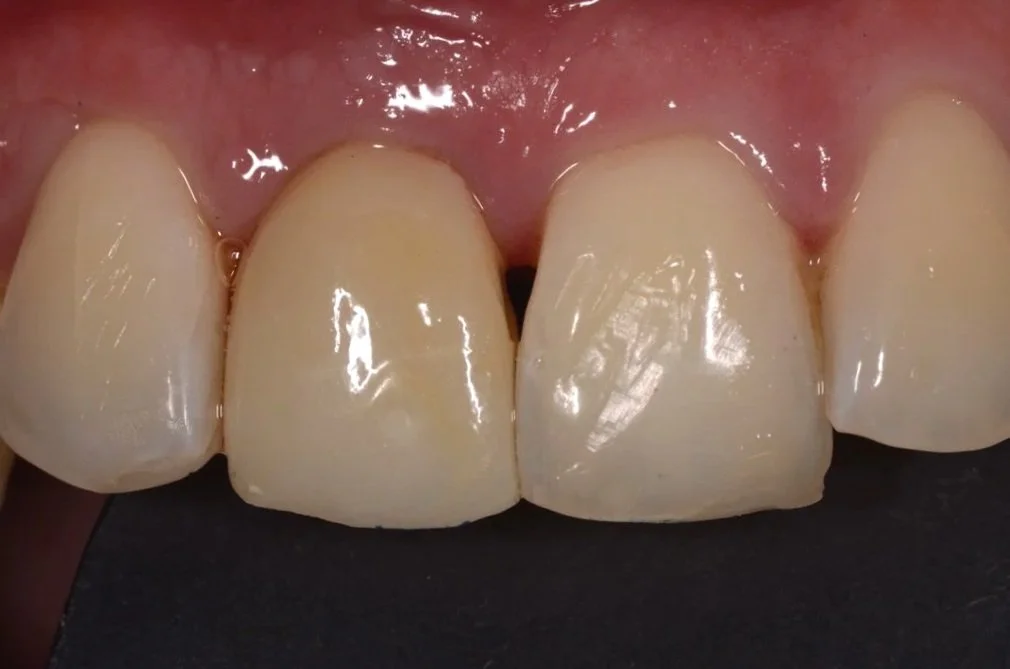

Fotografía inicial